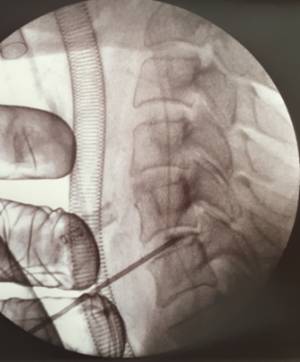

Mitjançant una mínima incisió a la pell i un endoscopi de menys de 5 mm de diàmetre es poden visualitzar totes les estructures de la columna cervical i abordar l'hèrnia discal de manera segura. La visualització de totes les estructures anatòmiques de la columna, mitjançant una càmera d'alta definició i irrigació contínua, facilita al cirurgià un treball segur i precís a la columna cervical. El Morgenstern Institute of Spine va ser pioner a practicar aquest tipus d'intervencions a la columna lumbar amb resultats excel·lents i ara l'ha aplicat amb èxit a la columna cervical per tractar una triple hèrnia discal cervical.